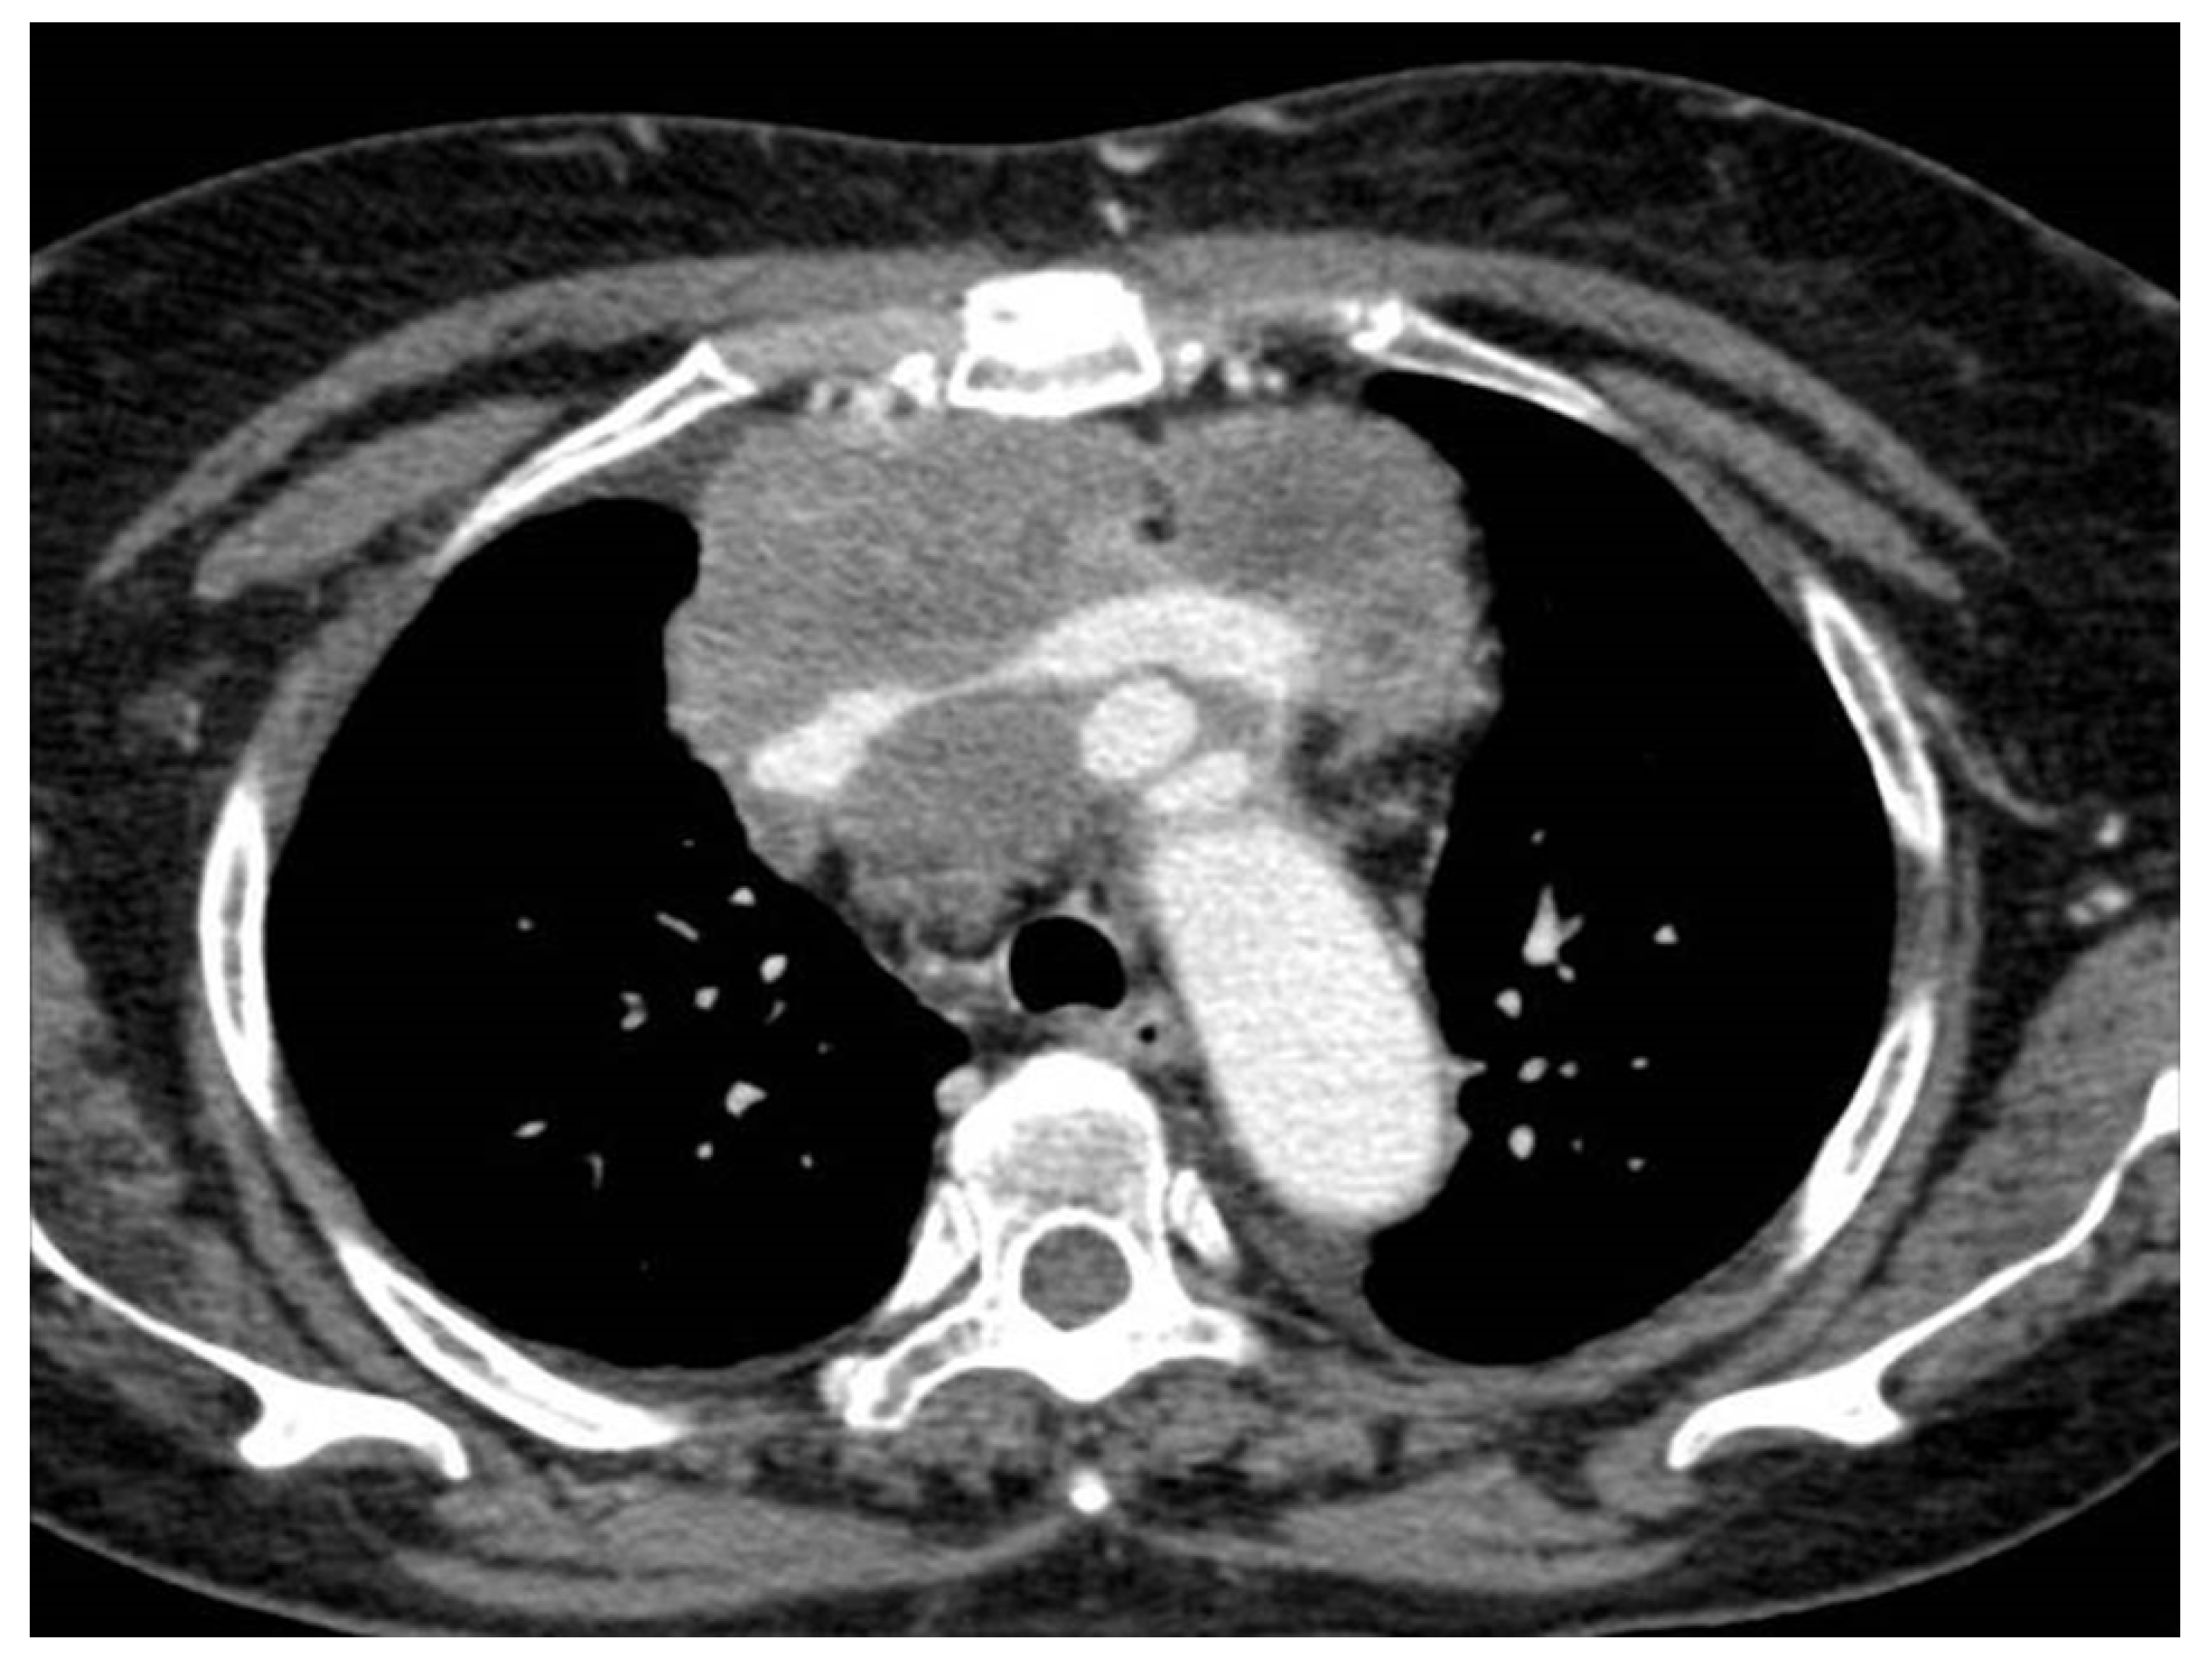

3. Unusual Radiological Presentation